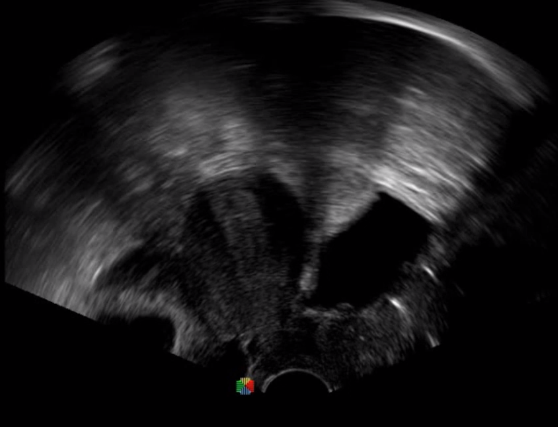

1生殖專用探頭

傳統(tǒng)腔內(nèi)探頭采用直柄設(shè)計(jì),在搭配穿刺架使用時(shí),手術(shù)空間小,不易操作;生殖專用的曲柄探頭,探頭柄采用彎曲成角度設(shè)計(jì),可實(shí)現(xiàn)監(jiān)視、取卵兩不誤,搭載穿刺架時(shí),可以清晰顯示穿刺針的進(jìn)針過程、深度和位置,實(shí)時(shí)監(jiān)視取卵全過程,保障取卵操作精準(zhǔn)與安全。

取卵臨床圖